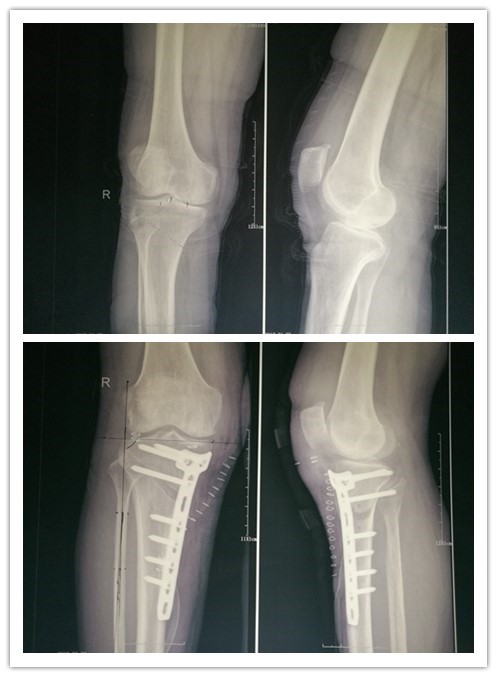

近日我院骨四科完成了首例胫骨高位截骨术(HTO)治疗膝关节骨关节炎,患者女性,61岁,右膝关节肿痛、屈伸活动受限半年,半年来患者行保守治疗,疼痛症状未见好转,入院诊断:右膝骨关节炎。

燕飞主任医师看过病人后考虑到患者有行全膝关节置换或半膝置换等二次手术的可能,查体患者只有膝关节内侧负重后疼痛,建议患者行保膝手术治疗。

研究证实开放楔形胫骨高位截骨,采用低切迹锁定钢板固定,能够有效矫正患者的膝关节畸形,并且短期随访临床效果较好。